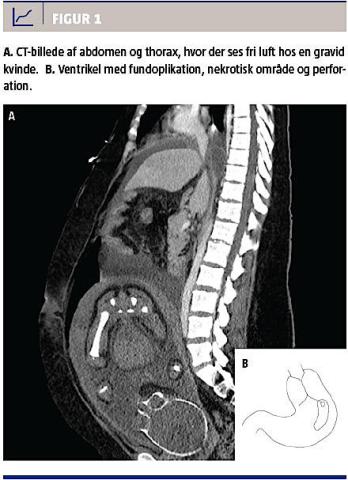

Patienten blev efter den initiale behandling tilset af en endokrinolog. Der var respons på behandling med glukose og insulin, men i løbet af aftenen forværredes hendes tilstand, og hun blev overflyttet til intensivafdelingen. Der blev endvidere foretaget en CTG med usikker føtal hjerterymte og en ultralydundersøgelse, hvor man ikke kunne visualisere sikre føtale bevægelser eller hjerteaktivitet. Der blev foretaget en samlet vurdering, hvor det blev besluttet at foretage CT af abdomen og thorax. CT’en viste fri luft, og på denne baggrund blev der planlagt kejsersnit i midtlinjeincision og foretaget eksplorativ laparotomi (Figur 1). Ved kejsersnittet blev der forløst et livløst foster, der ikke responderede på genoplivning. Ved laparotomien fandt man en ventrikel med 2 × 5 cm nekrose og perforation samt en snørefure under fundoplikationen. Fundoplikationen blev nedbrudt, ventriklen mobiliseret og den nekrotiske del af ventriklen reseceret.